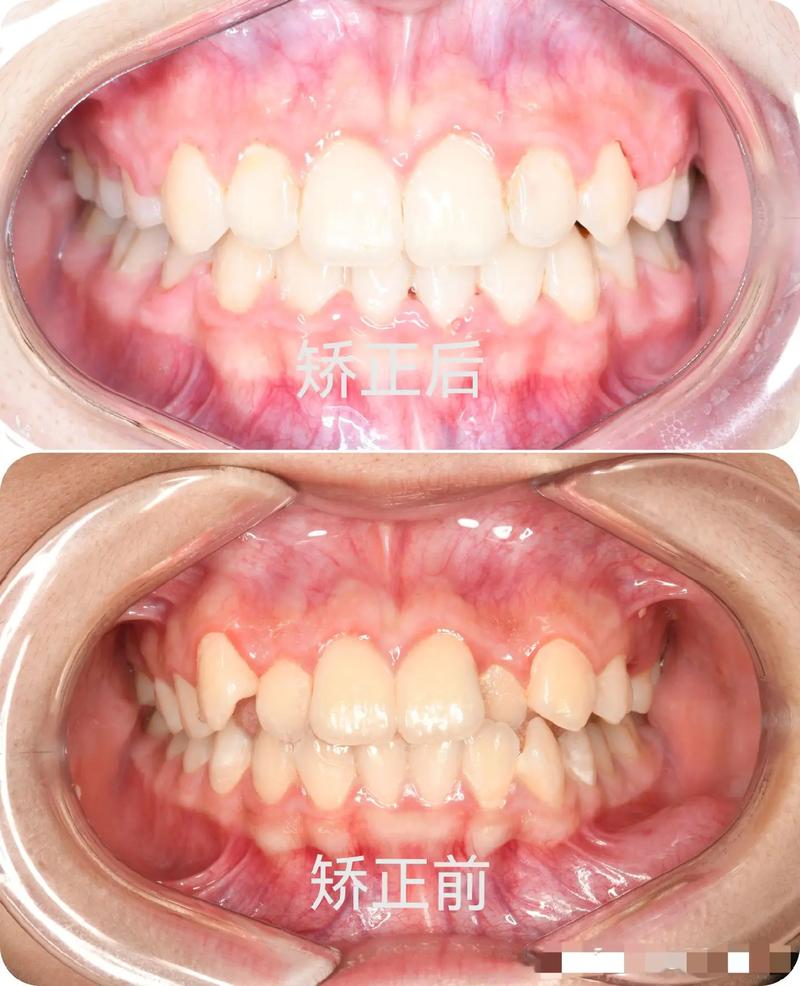

| 上颌前牙前突(深覆盖) | 自然状态下上前牙超出下前牙唇侧超过3mm,微笑时露龈过多,鼻唇沟明显,影响面部美观。 | 内收前牙,改善前突程度,建立正常覆颌覆盖(上前牙盖下前牙1/3-1/2)。 |

- 精细调整期(2-3个月):关闭间隙后,调整牙齿的咬合接触点、邻接关系及微笑曲线,确保功能与美观达到最佳状态。

问题2:拔2号牙会影响面型美观吗?比如会让嘴唇变瘪?